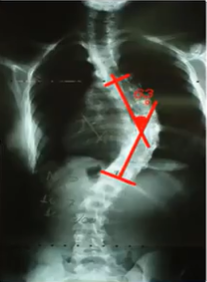

Qual exame para medição da escoliose?

Radiografia panorâmica (inclui toda a coluna)

Como medir a escoliose?

A maneira de medir é a partir do Ângulo de Cobb (linha a partir do corpo vertebral mais apical, em seguida uma linha a partir do corpo vertebral mais caudal. Por fim, traçamos linhas perpendiculares a cada uma dessas. O ponto de encontro forma o Ângulo de Cobb)